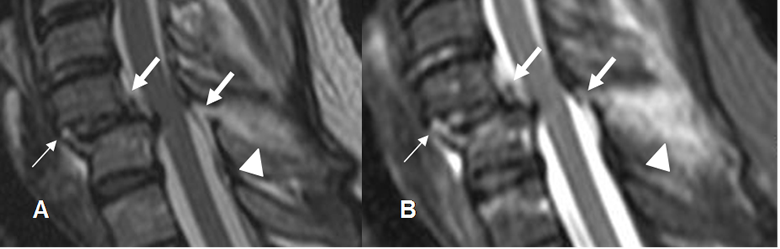

Fig 176 A. Lesión ligamentaria.

A: RM sagital en T2 y B: RM sagital en STIR. Luxación de facetas articulares, con anterolistesis de C5, sobre C6. Ligamento común anterior rodeado por líquido, pero permanece íntegro. (Flechas delgadas). Interrupción de los ligamentos común posterior y amarillo, por ruptura. (Flechas gruesas). Edema en los tejidos blandos posteriores, por lesión de los ligamentos interespinosos.

(Puntas de flecha.). Se aprecia escaso líquido anterior al cuerpo de C6.

Fig 176 B. Lesión ligamentaria.

A: TAC reconstrucción lateral y B: RM sagital en T2. Anterolistesis traumática, con aumento del espacio retrofaringeo y colección anterior. Adelgazamiento del ligamento común anterior (Flechas delgada) y ruptura del posterior. (Flecha gruesa). Adicionalmente hay compresión y alteración en la señal medular, por edema. (Puntas de flecha).